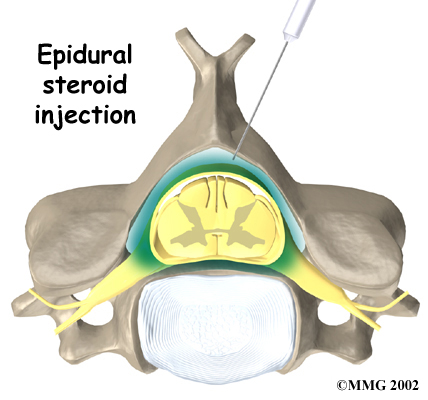

Injections

Spinal injections are used for both treatment and diagnostic purposes. There are several different types of spinal injections that your doctor may suggest. These injections usually use a mixture of an anesthetic and some type of cortisone preparation. The anesthetic is a medication that numbs the area where it is injected. If the injection takes away your pain immediately, this gives your doctor important information suggesting that the injected area is indeed the source of your pain. The cortisone decreases inflammation and can reduce the pain from an inflammed nerve or joint for a prolonged period of time.

Some injections are more difficult to perform and require the use of a fluoroscope. A fluoroscope is a special type of X-ray that allows the doctor to see an X-ray picture continuously on a TV screen. The fluoroscope is used to guide the needle into the correct place before the injection is given.

Epidural Steroid Injection: Neck pain or pain that spreads down the arm may require treatment with an epidural steroid injection (ESI). In an ESI, the medication mixture is injected into the epidural space around the nerve roots. Generally, an ESI is given only when other nonoperative treatments aren't working. ESIs are not always successful in relieving pain. If they do work, they may only provide temporary relief.

Epidural Steroid Injection: Neck pain or pain that spreads down the arm may require treatment with an epidural steroid injection (ESI). In an ESI, the medication mixture is injected into the epidural space around the nerve roots. Generally, an ESI is given only when other nonoperative treatments aren't working. ESIs are not always successful in relieving pain. If they do work, they may only provide temporary relief.

- Selective Nerve Root Injection: Another type of injection to place steroid medication around a specific inflamed nerve root is called a selective nerve root injection. The fluoroscope is used to guide a needle directly to the painful spinal nerve. The nerve root is then bathed with the medication. Some doctors believe this procedure gets more medication to the painful spot. In difficult cases, the selective nerve root injection can also help surgeons decide which nerve root is causing the problem before surgery is planned.

- Facet Joint Injection: When the problem is thought to be in the facet joints, an injection into one or more facet joints can help determine which joints are causing the problem and ease the pain as well. The fluoroscope is used to guide a needle directly into the facet joint. The facet joint is then filled with medication mixture. If the injection immediately eases the pain, it helps confirm that the facet joint is a source of pain. The steroid medication will reduce the inflammation in the joint over a period of days and may reduce or eliminate your neck pain.

- Trigger Point Injections: Injections of anesthetic medications mixed with a cortisone medication are sometimes given in the muscles, ligaments, or other soft tissues near the spine. These injections are called trigger point injections. These injections can help relieve neck pain and ease muscle spasm and tender points in the neck muscles.